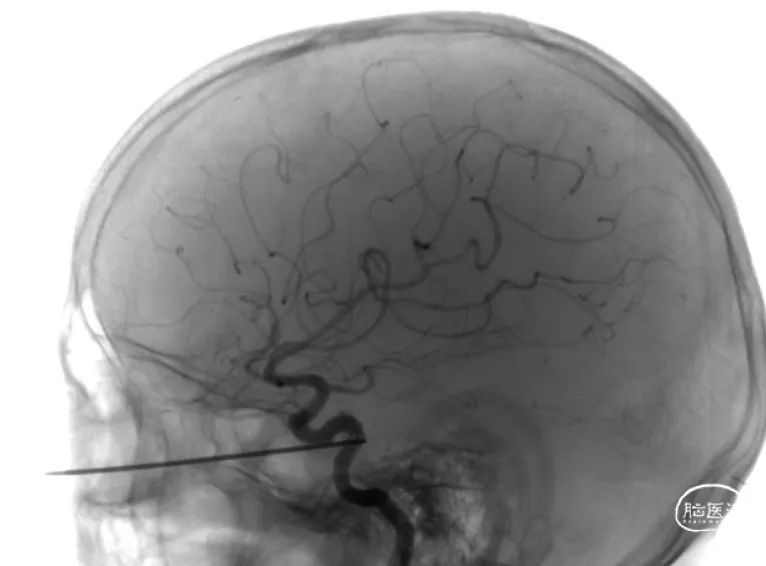

手术当天,余果副教授先进行血管造影。重建的影像再次确认金属棒压迫颈内动脉。当BOT实验及加强实验证实“对侧血管代偿良好”时,整个团队都松了一口气:在万不得已的情况下,至少可以通过闭塞血管挽救患者生命。花玮教授、吴雪海教授、朱侗明及张金森医生负责内镜下操作,朱巍教授全程指导。

内镜下逐步分离后,医生看到金属棒通过海绵窦的“安全三角”进入窦内,解释了为何患者尚未出现严重的症状。极其细致、缓慢拔除金属棒后,大量血液自破口内涌出,紧急压迫止血后进行血管造影,未见明确动脉破裂。治疗团队决定不再进行颈内动脉闭塞,尝试内镜下止血。为了更有效地止血,团队在内镜下逐步去除压迫物后,将常规的材料压扁揉搓成米粒大小的致密止血材料,替代填塞止血,最终成功止住破口的出血。手术结束后再次造影,未见动脉破裂及颈内动脉海绵窦瘘。再看时钟,已经十个小时过去了。